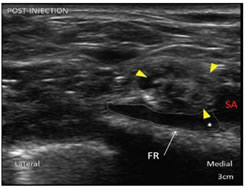

Figure 6                                                                           Figure 7

Figure 6: View on the USG screen before injection of local anesthetic drug; Figure 7: Postanesthetic injection: Right supraclavicular brachial plexus (yellow arrows)

Brachial plexus = yellow arrows. FR = first rib, SA = subclavian artery, P = pleura, * = corner pocket. Local anesthetic (dashed lines) had been deposited in corner pocket (*). Note the nerves now appeared to be floating on the injected anesthetic drug. FR = first rib, SA = subclavian artery.

Patients were positioned supine with head end elevated , head turned towards the opposite side and the arm to be blocked was kept adducted by the side of patient. Sterile painting and draping were done. USG linear probe of 7-10 MHz was used to locate the brachial plexus. After applying sterile jelly the probe was moved from cephalic to caudal direction to bring subclavian artery in the center of the screen to a point where nerve plexus was situated lateral to artery (Figure 6). A 20G 100mm Quinckie spinal needle was inserted from lateral to medial direction by using in plane technique so that needle remains visible at any point of time and injury to pleura can be prevented. Combination of Inj. Bupivacaine 0.5 % and Inj. Lidocaine 2 % was used. Total 25 ml of local anaesthetic solution was taken (15 ml of Inj. Bupivacaine and 10 ml of Inj. Lidocaine). Once the needle was between brachial plexus and artery, half of the solution of local anesthetic was injected first in corner pocket, i.e. at 7’O clock position of subclavian artery and remaining half of the local anesthetic solution was injected in the superior pocket i.e. 11’O clock position of the subclavian artery after redirecting the needle (Figure 7).